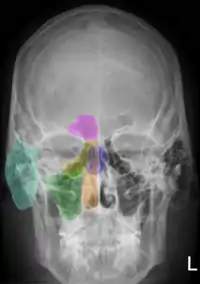

Рентгеноанатомия органов грудной клетки.

Рентгеноанатомия органов грудной клетки. Зелёным обозначены трахея и крупные бронхи, синим — ветви лёгочных артерий, красным — дуги тени сердца, цифрами отмечены сегменты лёгких.